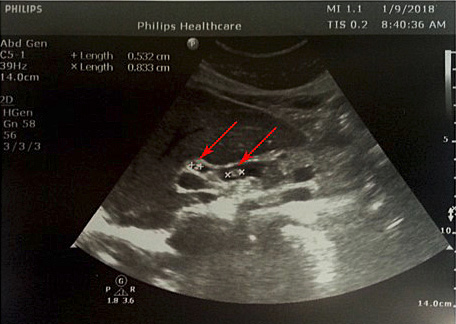

1 pav. Prisipildymo defektas (helmintas) BTL (pažymėta rodyklėmis), nesant echogeninio šešėlio

Atlikus ultragarsinį pilvo tyrimą, konstatuota, kad tulžies pūslė pašalinta, BTL 0,8–1,0 cm pločio. Jo spindyje pastebėtos hiperechogeniškos masės (0,6–0,8 cm skersmens), distaliniame gale susiliejančios į didesnes sankaupas (1, 2 pav.). Kitų vidaus organų ir struktūrų matomų patologinių pokyčių nenustatyta.

Sergant tulžies latakų askaridoze, kraujo tyrimai gali atitikti normos ribas. Tokiu atveju įtarti patologiją padeda paciento nusiskundimai, išsami ligos ir gyvenimo anamnezė (kelionės, namų aplinka, valgymo įpročiai ir sąlytis su dirvožemiu). Specifinių (ligą diagnozuojančių) laboratorinių tyrimų askaridozei nustatyti nėra. Tiksliai diagnozuoti parazitų invaziją į žarnyną, kai laboratoriniai tyrimai nepatologiniai, galima identifikavus askaridžių kiaušinėlius paciento išmatose [3, 27]. Kirmėlių migraciją į tulžies latakus galima nustatyti atlikus ultragarsinį tyrimą. Dažnai ultragarsu pastebimas prisipildymo defektas BTL. Jis būna pailgos arba cirkuliarios formos, be tulžies latakų akmenims būdingo šešėlio – artefakto. Dėl šios priežasties ultragarsu stebimas prisipildymo defektas dar vadinamas „minkštu“ radiniu (1, 2 pav.). Nors ultragarsinis tyrimas vertinamas kaip jautrus ir specifiškas (atitinkamai 40–70 proc. ir 90 proc.), tyrimo kokybė priklauso ir nuo tyrėjo patirties. Tulžies latakuose esant oro po buvusių intervencijų arba kirmėlių maceracijos metu, kai kirmėlė negyva, ji gali būti nepastebėta [2, 3].